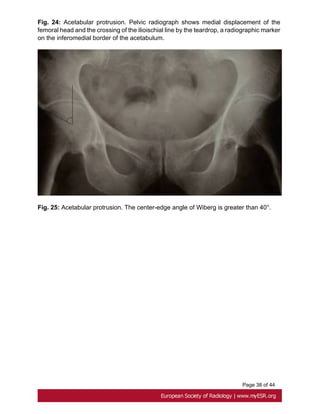

Fig. 24: Acetabular protrusion. Pelvic radiograph shows medial displacement of the

femoral head and the crossing of the ilioischial line by the teardrop, a radiographic marker

on the inferomedial border of the acetabulum.

Fig. 25: Acetabular protrusion. The center-edge angle of Wiberg is greater than 40°.

Page 12 of44 CT scanning is commonly used for this purpose but MRI and even standard radiographs, with anteroposterior and lateral incidences, have a high diagnostic accuracy. [36, 37]. - Pectus carinatum, an anterior protrusion of the upper portion of the sternum, does not narrow the anterioposterior diameter of the chest and therefore does not displace the heart. It is usually repaired for cosmetic reason[38]. • Acetabular Protrusion Intrapelvic acetabular protrusion is a deformity of the hip joint in which the medial wall of the acetabulum invades the pelvic cavity with associated medial displacement of the femoral head [39]. Progressive protrusion can lead to early osteoarthritis by a loss of posteroinferior joint space[40]. Acetabular protrusion can be assessed with three methods on pelvic radiographs: - the crossing of the ilioischial line by the teardrop, a radiographic marker on the inferomedial border of the acetabulum just superior to the obturator foramen [40]. Fig. 24 on page 37 -the center-edge angle of Wiberg : an angle between a vertical line drawn through the center of the femoral head and another line drawn from the center of the femoral head through the lateral margin of the acetabulum is greater than or equal 40° Fig. 25 on page 38 -the acetabular-ilioischial distance is greater than or equal to 3 mm in men and greater than or equal to 6 mm in women (method of Armbuster)[41, 42]. Treatment of this abnormality comprises both conservative ( weight extension on an abduction frame and reeducation) and surgical methods. • Arachnodactyly Arachnodactyly is a very common characteristic of Marfan syndrome. The metacarpal index is calculated by the average central length of the second to fifth metacarpals divided by the average narrowest widths of the second to fifth metacarpals. An index greater than 8,4 is considered abnormal [12, 44]. Fig. 26 on page 38

Page 38 of44 Fig. 24: Acetabular protrusion. Pelvic radiograph shows medial displacement of the femoral head and the crossing of the ilioischial line by the teardrop, a radiographic marker on the inferomedial border of the acetabulum. Fig. 25: Acetabular protrusion. The center-edge angle of Wiberg is greater than 40°.